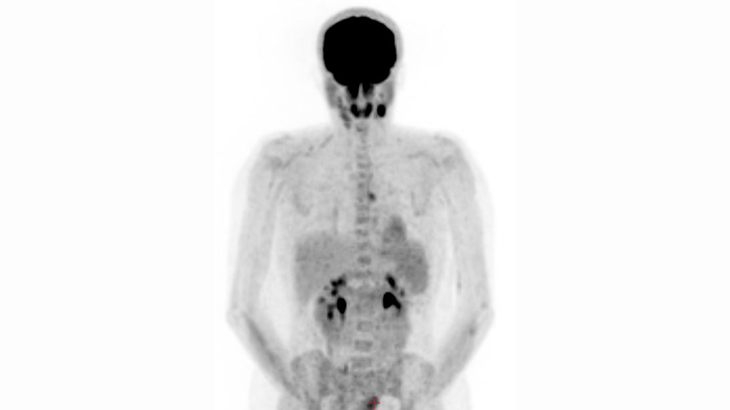

A Positron Emission Tomography-Computerized Tomography (PET-CT) scan helps to see if there is active cancer in your body. It also helps to see if the cancer has spread. The scan also helps in the assessment of how you responded to the cancer treatment.

PET-CT involves the injection of a small amount of radioactive sugar called FDG into your vein, followed by obtaining "pictures" of your body. Because tumor cells are typically more active than normal cells and they need sugar to grow, the tumor cells will take up the radioactive sugar and essentially "light up" on the scan. This allows the PET-CT camera to take highly specialized pictures and image the radioactivity within the tumor cells.